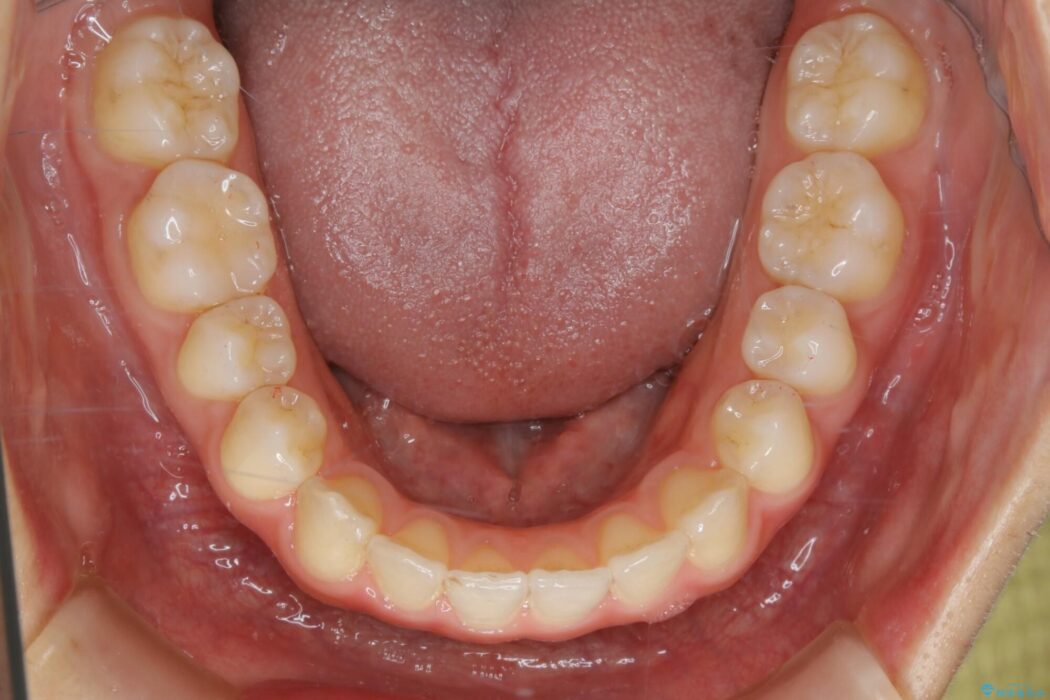

治療後写真を見ても歪みが解消され、歯列弓がきれいに整ったのが分かると思います。インビザラインをしっかりと装着されていたこともあり、矯正としては短期間の治療となりました。